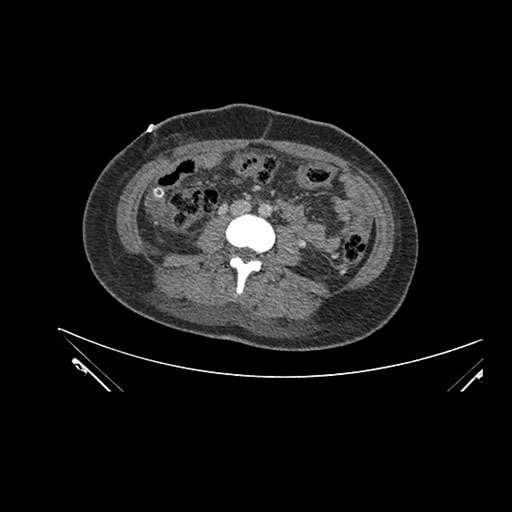

Imaging Analysis

Look through the patient's CT scan to identify any areas of concern for the necessary procedure.

Axial Arterial

Based on initial findings, which issue(s) would you be most concerned about?